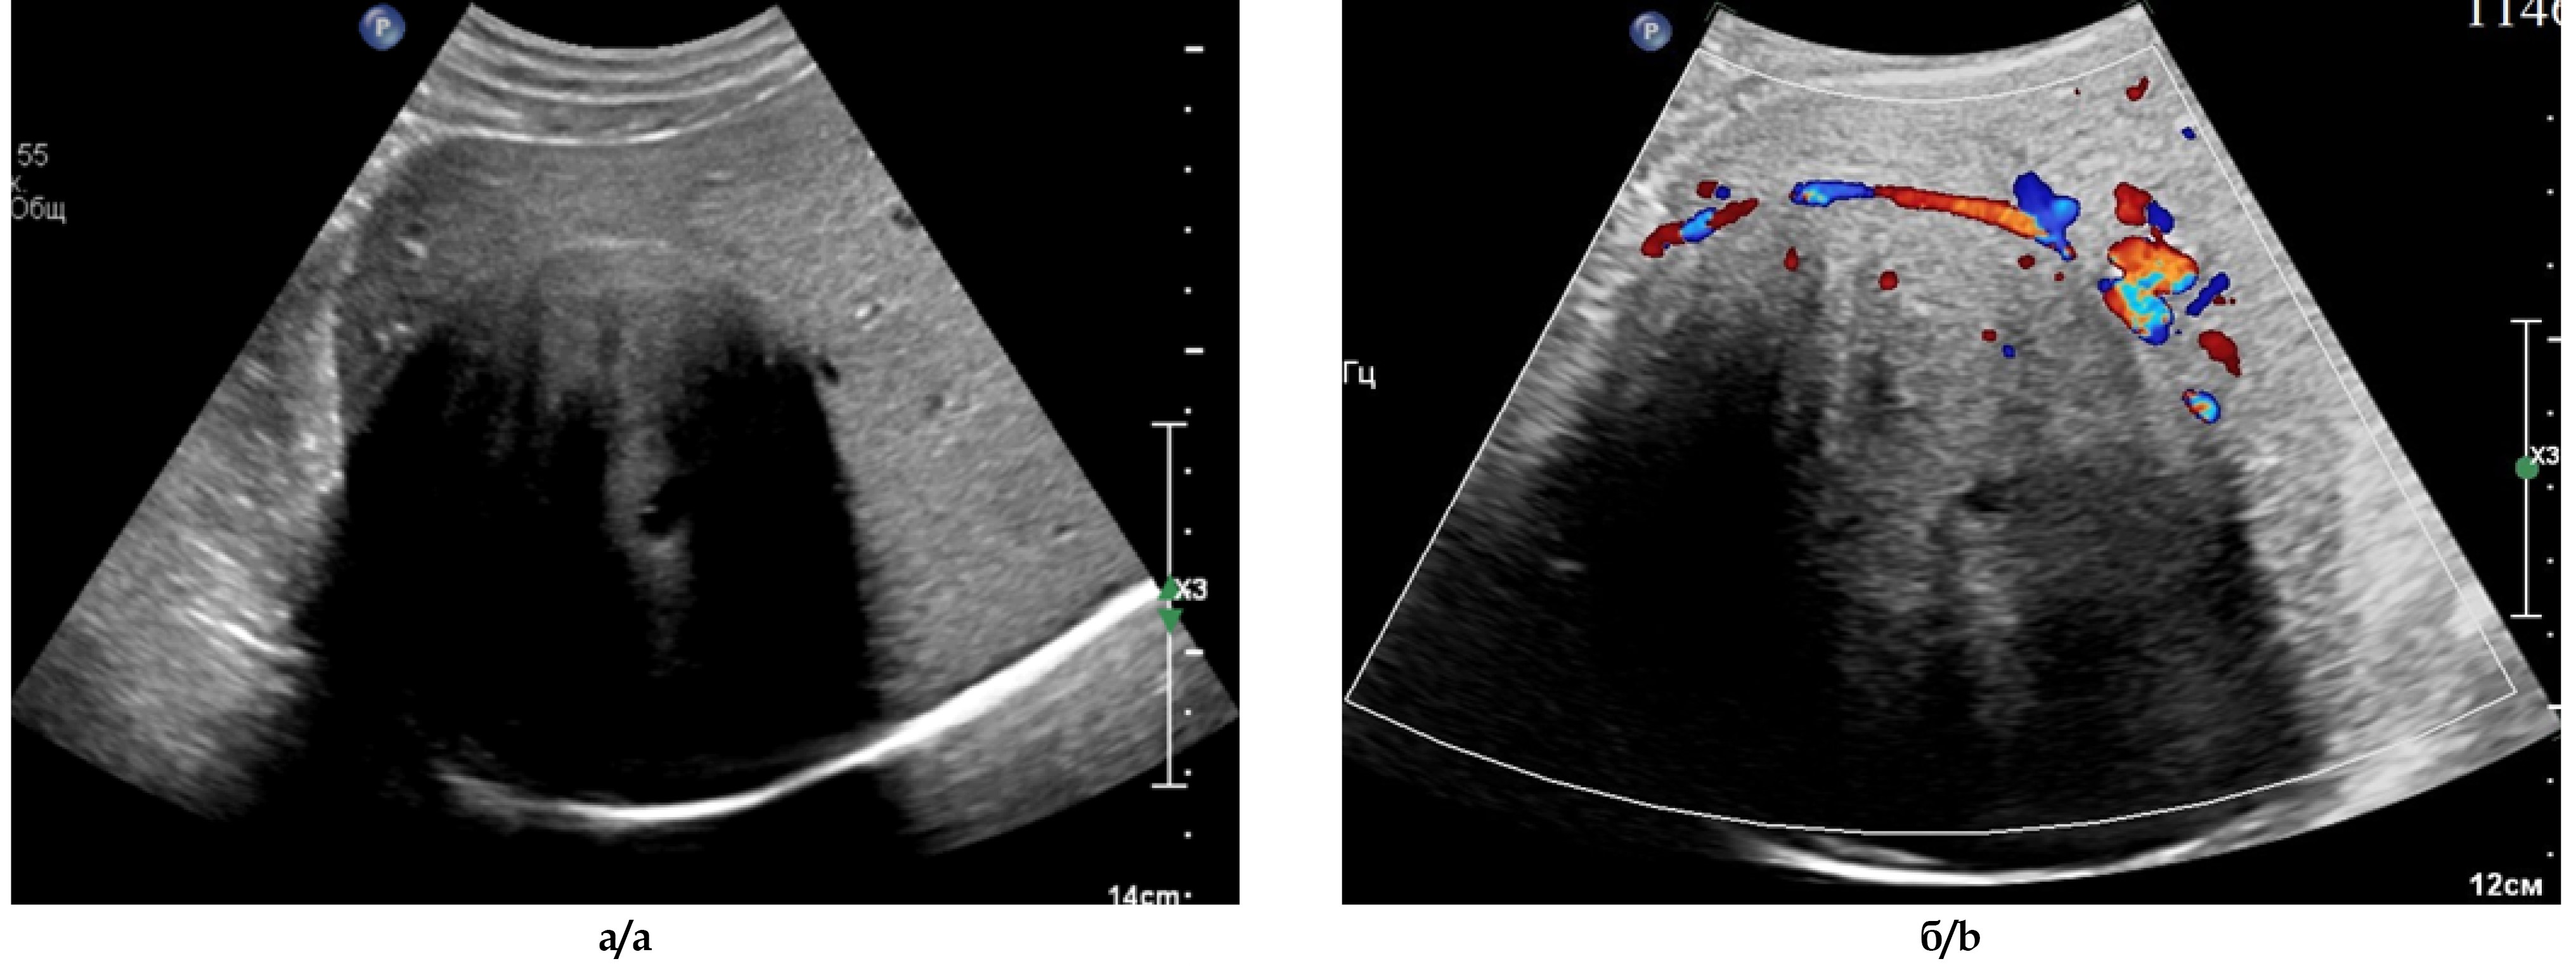

Ультразвуковое исследование брюшной полости и почек. Печень в размерах увеличена: передне-задний размер правой доли – 172,0 мм, левой доли – 70,3 мм, контуры чёткие ровные, паренхима повышенной эхогенности, отмечается незначительное затухание эхосигнала к периферии. В правой доле печени, в проекции VI-VII сегментов, визуализируется образование, размерами 94,9х79,9х95,3 мм, с четкими, ровными контурами, выраженным количеством акустических теней и, на этом фоне, значительным затуханием эхосигнала к дистальной части опухоли (рис. 3а). Структура образования солидая неоднородная, с наличием в центральном сегменте нескольких мелких кистозных полостей. Образование кровоснабжается из сегментарных ветвей правой ветви собственной печёночной артерии и воротной вены. Кровоток в структуре образования смешанного неравномерного типа, лоцируется только по переднему контуру, что обусловлено наличием слившихся акустических теней в задней части опухоли (рис. 3б).

Рис. 3. УЗ-изображения опухоли печени: а - в В-режиме, б - в режиме цветового допплеровского картирования.

Fig. 3. US of the tumor: a – B-mode, b – Doppler mode.

Заключение. Объемное образование правой доли печени (гепатоцеллюлярный рак?), однако, обращает на себя внимание наличие сливающихся акустических теней по периферии опухоли. Увеличение размеров и диффузные изменения паренхимы печени по типу жирового гепатоза. Мелкие ангиомиолипомы обеих почек.